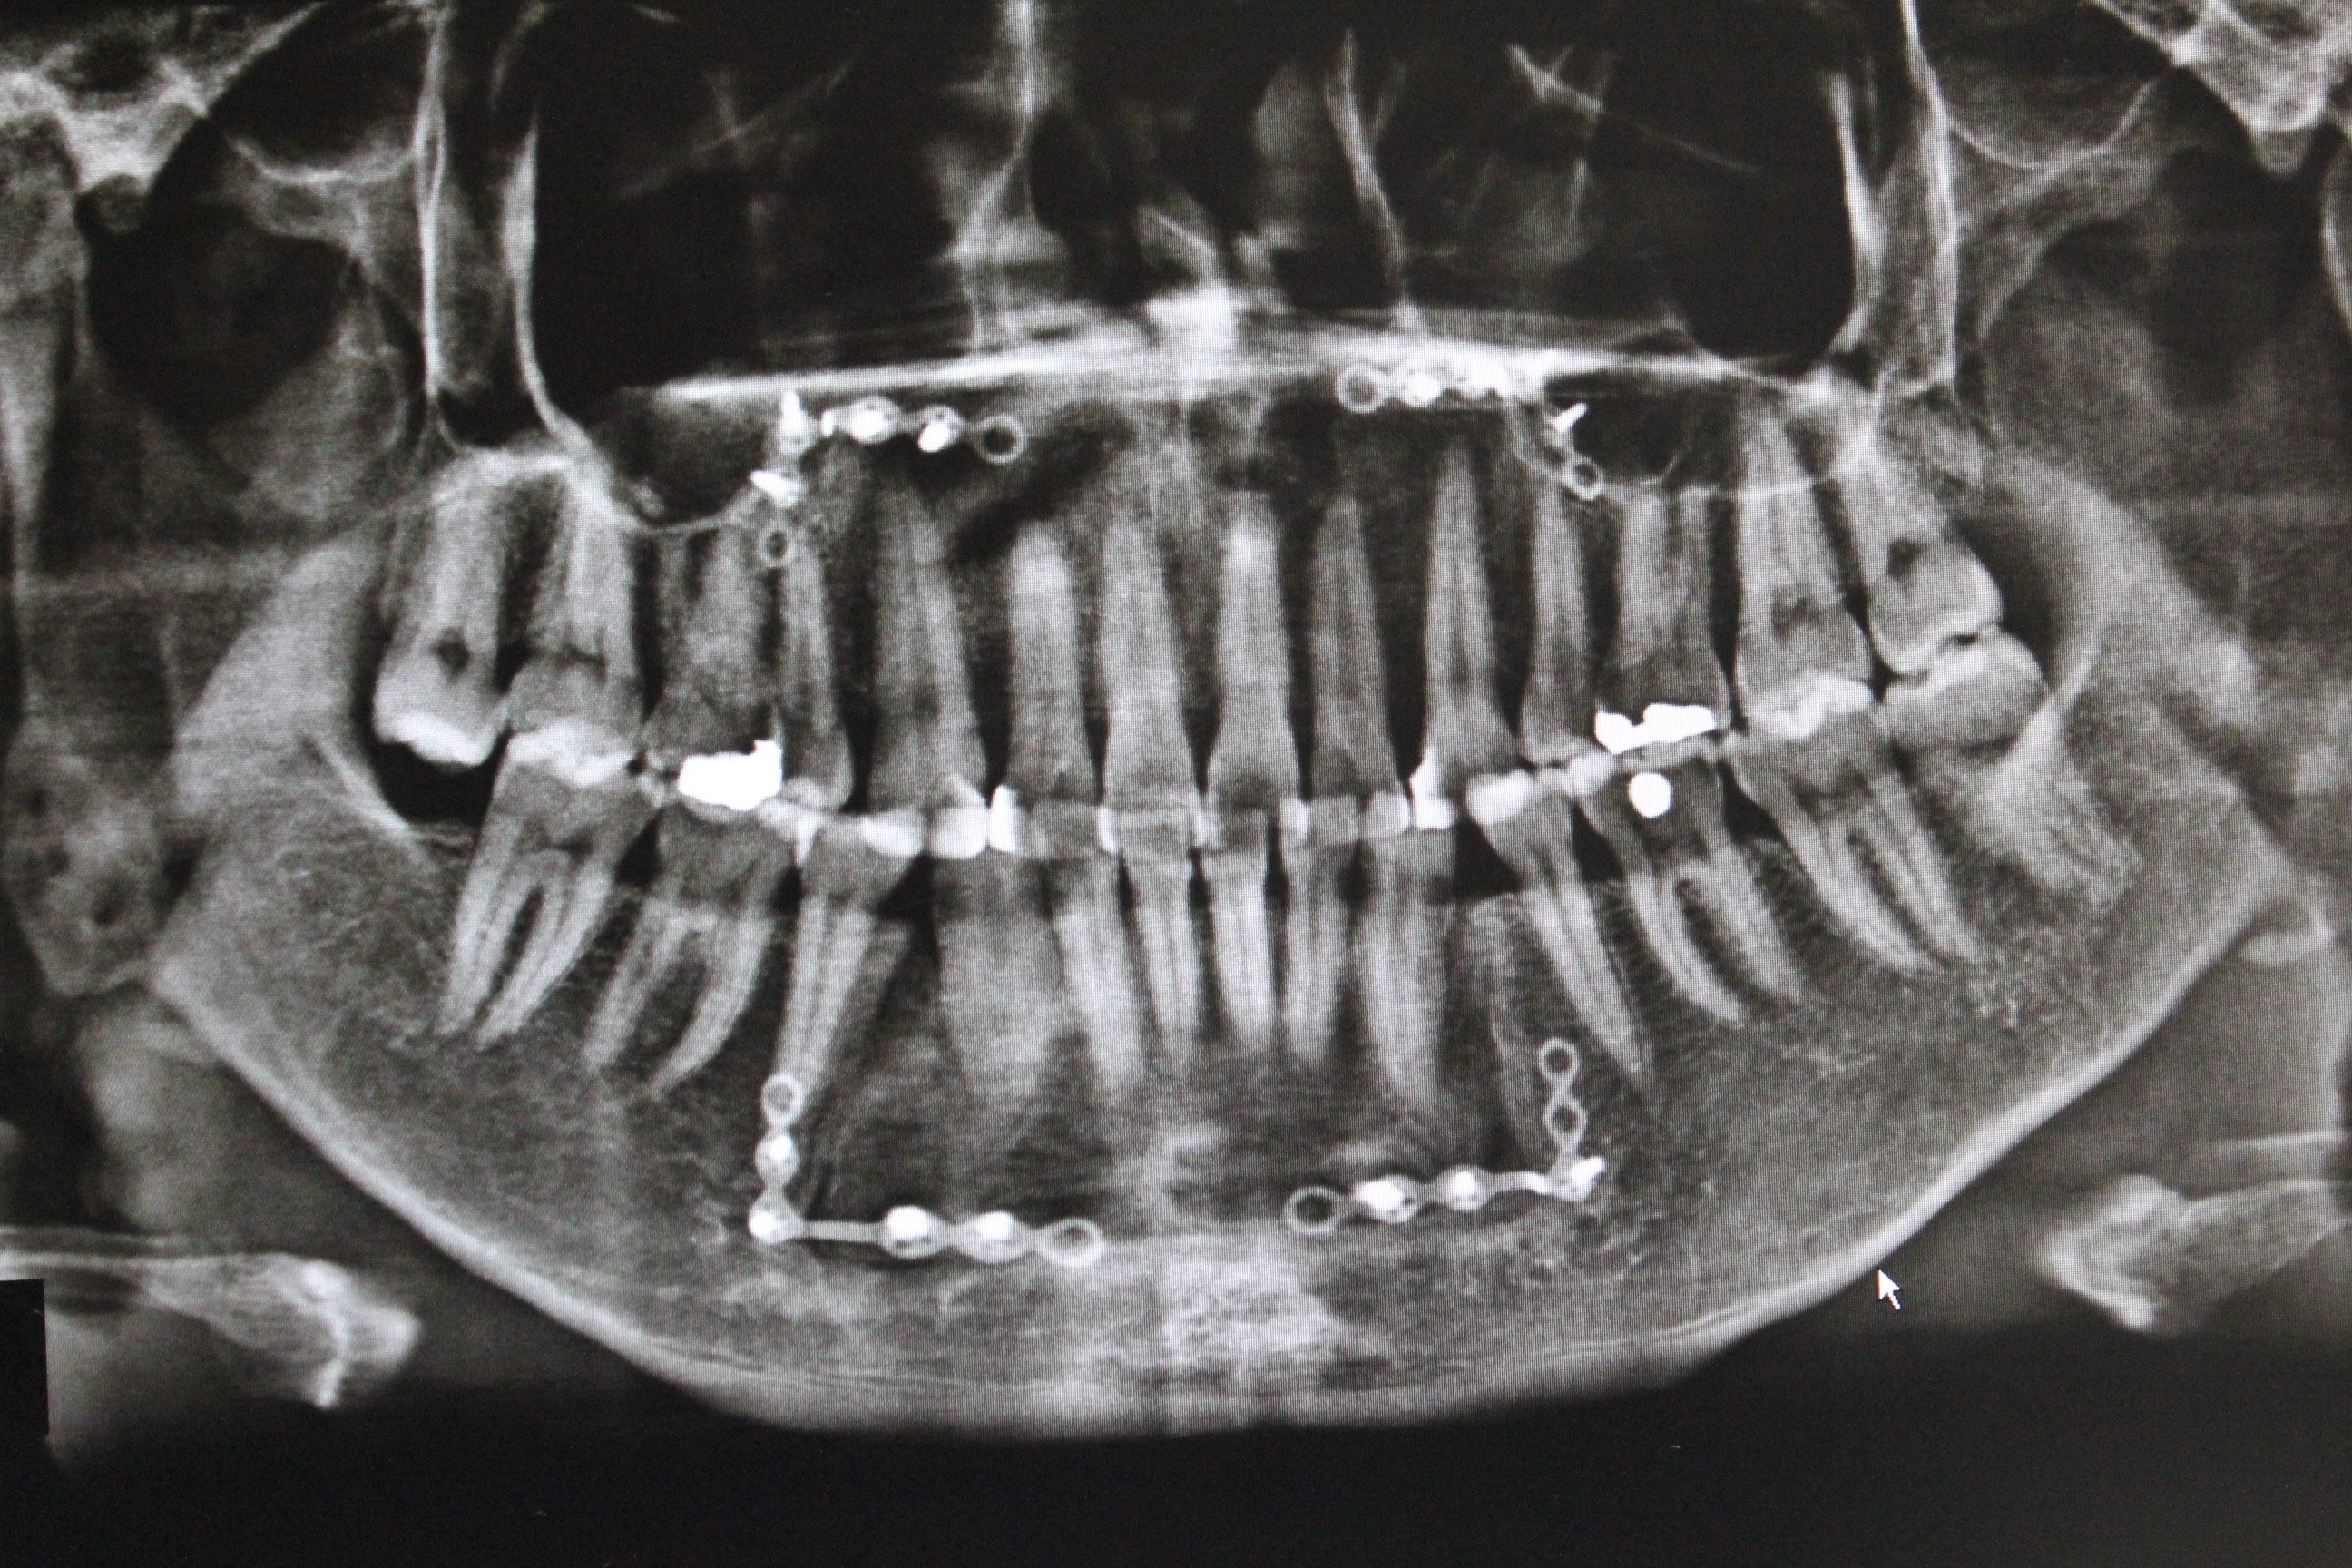

수술후 - 파노라마 엑스레이